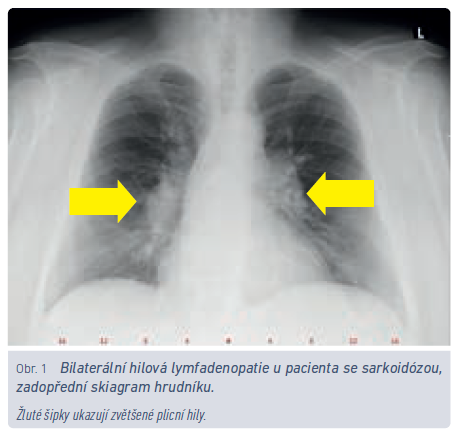

Typickým zástupcem nemocí provázených granulomatózním plicním postižením je sarkoidóza. Lze namítnout, že etiologii sarkoidózy neznáme, tudíž proč ji nezmínit v rámci skupiny předchozí, odlišnost sarkoidózy ale spočívá v jejím potenciálu postihovat i jiné orgány než jen plíce. I když u některých nemocných může mít sebelimitující průběh (Löfgrenův syndrom – erythema nodosum, subfebrilie, bilaterální hilová lymfadenopatie), postihne‑li mozek nebo srdce, nejenže sama nezmizí, ale může být pro postiženého jedince fatální.

Roční incidence sarkoidózy v ČR je udávána 3,1/100 000 obyvatel, prevalence světově 6–23,1/100 000 obyvatel.8 Pro srovnání, prevalence chronické obstrukční plicní nemoci (CHOPN) v roce 2017 v ČR byla 21,6/1 000 obyvatel.9 Zatímco pacientů s CHOPN je tedy v ČR zhruba čtvrt milionu, nemocných se sarkoidózou může být 600–2 300. V případě akutního rozvoje sarkoidózy v podobě výše uvedeného Löfgrenova syndromu je velmi pravděpodobné, že onemocnění vymizí samo, bez nutnosti systematické léčby (obr. 1). Dominantním problémem u této skupiny nemocných bývá erythema nodosum v oblasti bérců a velmi často otoky a bolest kotníků. Nezřídka bývají nemocní léčeni antibiotiky (záměna s poštípáním hmyzem), odesíláni na kožní oddělení nebo k revmatologovi. Charakteristický nález bilaterální hilové lymfadenopatie společně s erythema nodosum pro diagnózu postačí, a je‑li propuknutí nemoci provázeno i systémovými příznaky (subfebrilie, febrilie), není pro stanovení diagnózy požadována histologická verifikace. Jsou‑li nemocnému v této fázi podány symptomaticky systémové kortikosteroidy, zvyšuje se riziko jak recidiv, tak přechodu do chronické formy.10